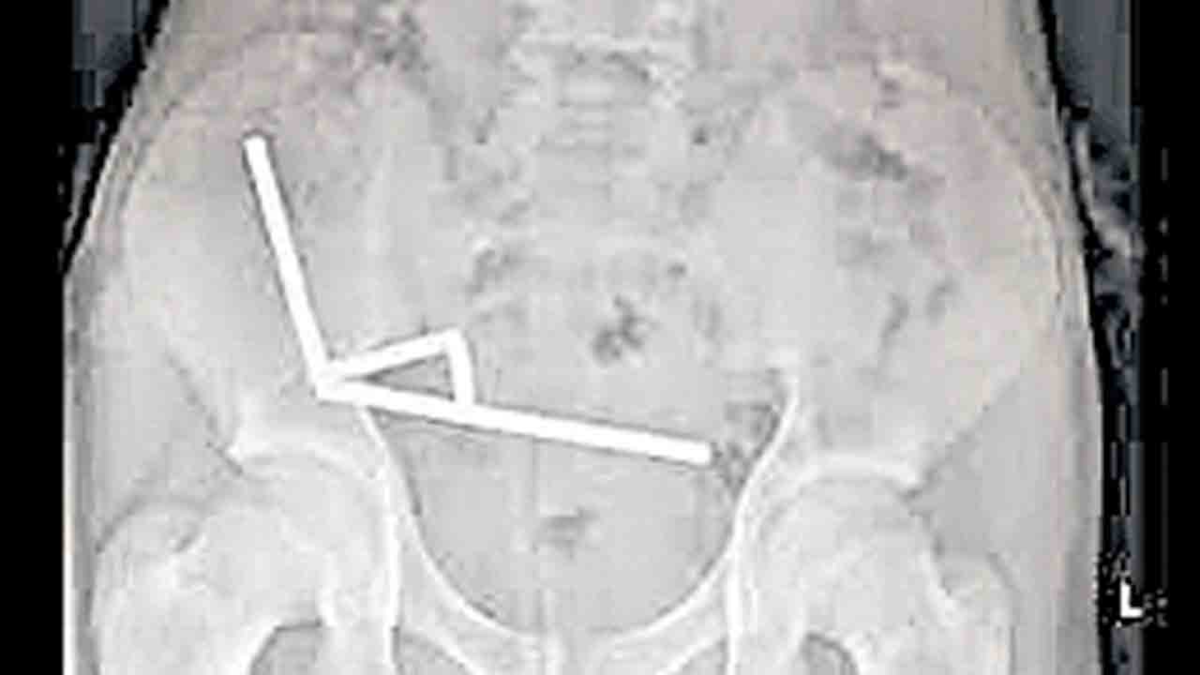

నవతెలంగాణ – హైదరాబాద్: న్యూజిలాండ్లోని వెల్లింగ్టన్లో 13 ఏళ్ల బాలుడు ఆన్లైన్లో కొనుగోలు చేసిన 100 అయస్కాంతాలను మింగడంతో తీవ్ర కడుపు నొప్పితో ఆసుపత్రిలో చేరాడు. ఎక్స్రేలో 80 నుంచి 100 అయస్కాంతాలు పేగుల్లో చిక్కుకుపోయి దెబ్బతిన్నట్లు వైద్యులు గుర్తించారు. 2013 నుంచి అక్కడ అయస్కాంతాలు నిషేధం ఉన్నా ఆన్లైన్లో విచ్చలవిడిగా అమ్ముతున్న టెము కంపెనీపై చర్యలు తీసుకోవాలని ఆ దేశ ప్రజలు డిమాండ్ చేస్తున్నారు.